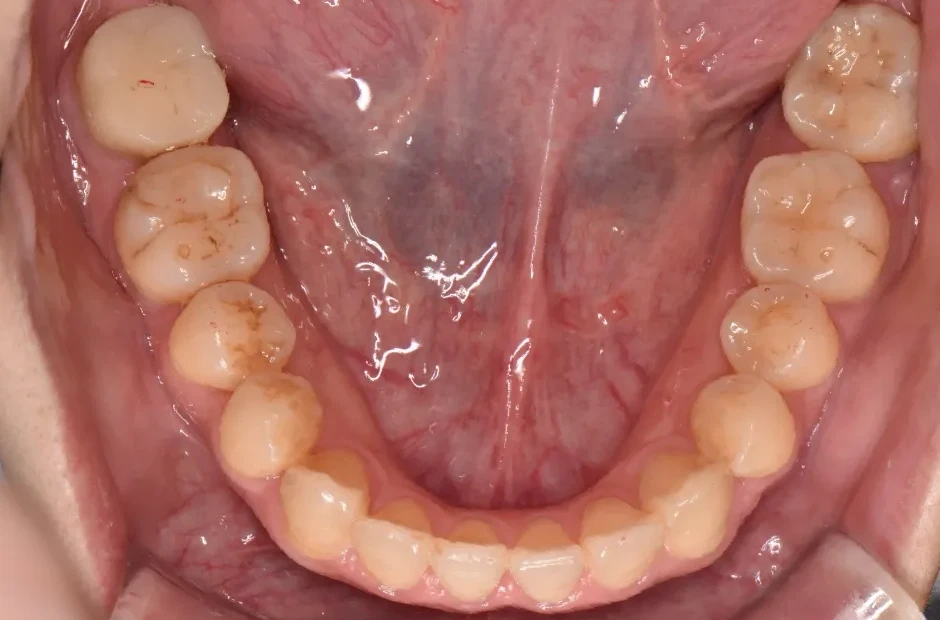

叢生

| 診断名・主訴 | 叢生 |

|---|---|

| 年齢・性別 | 43歳・女性 |

| 治療期間・回数 | 2年7か月 27回 |

| 治療に用いた主な装置 | 舌側矯正 |

| 抜歯部位 | 両顎4,4 |

| 治療費 | 100万円(税抜) |

| リスク・副作用 | 装置による違和感・疼痛・歯肉退縮・歯根吸収・虫歯のリスクなど |

治療前

治療中

治療後